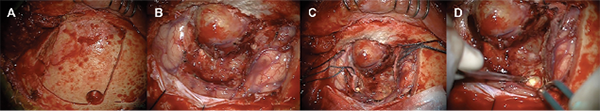

Ante la alta sospecha de absceso cerebral secundario a patología del seno frontal izquierdo y dado los hallazgos clínico-radiológicos, el paciente fue operado en las primeras veinticuatro horas desde su ingreso. Se realizó una incisión para abordaje pterional modificado, disección de colgajo pediculado de galea y periostio frontal y craneotomía frontal izquierda ajustada a reborde orbitario superior y línea media, con exposición del seno frontal ipsilateral.

Tras realizar la craneotomía frontal, se objetivó la integridad de la duramadre de la convexidad frontal y se identificó una lesión de características óseas en el interior del seno frontal compatible con osteoma. La apertura dural permitió reconocer una voluminosa lesión de bordes bien definidos, encapsulada, en aparente continuidad con la pared interna del seno frontal izquierdo. Dicha lesión, compatible con mucocele intracerebral, presentaba una ruptura en su vertiente posteromedial (Fig 2.) Del interior de la lesión encapsulada se obtuvo material mucoide/proteináceo que fue remitido para estudio microbiológico y anátomo-patológico. La colección fue resecada conservando la cápsula y posteriormente remitida para cultivo. Una vez aislada la lesión del parénquima cerebral, se procedió a su exéresis en bloque confirmando su continuidad con el interior del seno frontal izquierdo a través de un defecto dural frontobasal y óseo de la pared posterior del mismo (Fig 3).

Completada la exéresis de la lesión intracraneal, se procedió a la resección del osteoma intrasinusal frontal y preparado del seno para su sellado y reconstrucción. La consistencia del osteoma sinusal permitió su fresado con motor quirúrgico de alta velocidad y su exéresis hasta identificar el ostium a nivel mediobasal. La mucosa remanente en el interior del seno, de predominio posterior, fue resecada exhaustivamente hasta visualizar las superficies óseas intrasinusales de la pared externa del seno frontal y resto de pared interna. Finalizado el vaciado del seno frontal, se puso de manifiesto el defecto de la pared interna del mismo y la solución de continuidad de la duramadre frontobasal.

La reconstrucción y sellado del seno frontal se llevó a cabo con cemento artificial (Mimix-Walter Lorenz Surgical, Jacksonville, FL, USA). Una vez solidificado se procedió a cubrir el seno con un colgajo pediculado de galea y periostio frontal. Aisladas las cavidades paranasales, se completó el lavado del compartimento intracraneal y se procedió al cierre hermético de la duramadre frontal, reposición ósea y cierre por planos (Fig 3).

Fig 2. Imágenes intraoperatorias. A) Incisión pterional modificada con abordaje frontotemporal izquierdo. B-C) Disección microquirúrgica con exposición de lesión frontal basal (mucocele intracraneal) y osteoma frontal intrasinusal D) Colección abscesificada posteromedial al mucocele intracraneal.

Fig 3. Imágenes intraoperatorias. A) Osteoma frontal. El disector indica el punto de ruptura de la pared del seno y entrada del mucocele a la cavidad intracraneal. B) Fresado y vaciado del seno frontal izquierdo. El disector muestra la solución de continuidad C) Comunicación entre el seno frontal y el lecho del mucocele. D) El disector indica el defecto óseo de la pared posterior del seno frontal y el defecto dural frontobasal. E) Retracción fronto-basal y exposición del techo de la órbita. F) Sellado del seno frontal tras vaciado y exéresis de los restos de mucosa.